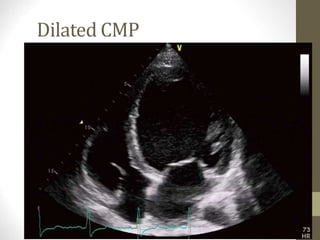

•Echocardiography : moderately

reduced systolic function, with dilated

LV ( features of dilated CMP ).

Investigations •CBC : Normal •Metabolicpanel : normal •ECG : left axis deviation •Echocardiography : moderately reduced systolic function, with dilated LV ( features of dilated CMP ).